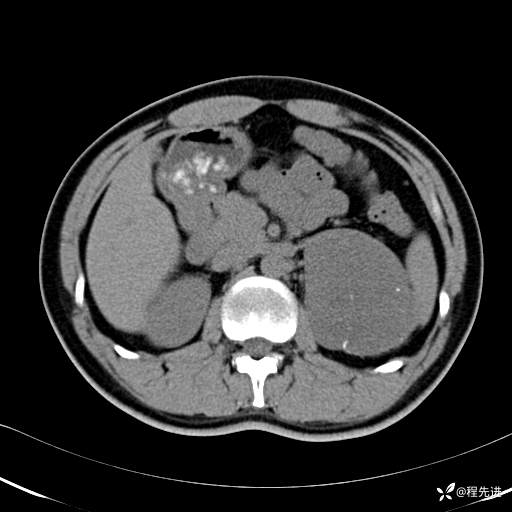

【腹盆】特别精彩病例|体检发现的左侧腹膜后占位期待您的精彩解读

患者年龄:25岁

简要病史:体检发现

CT平扫:(CT值:平扫,27HU,动脉期,27HU,门静脉期,31HU,平衡期,32HU)

CT增强:

动脉期: